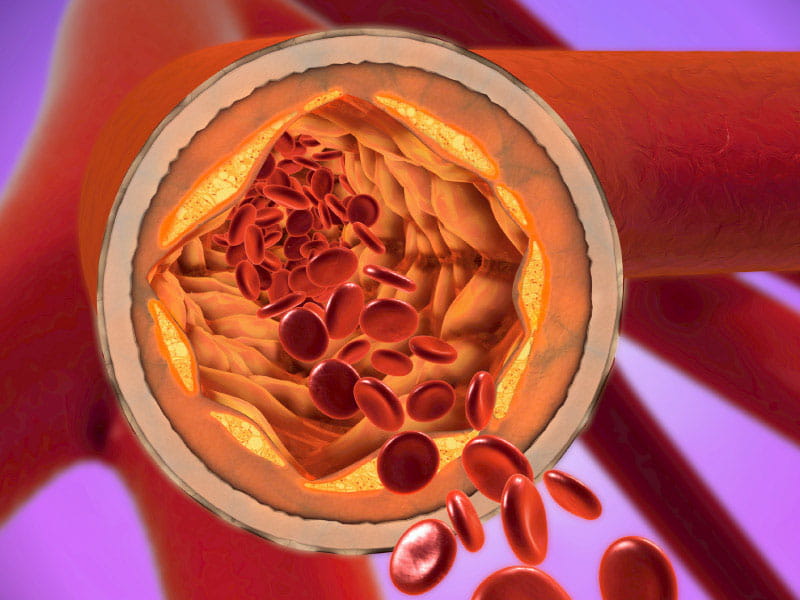

Lipoprotein(a), like low-density cholesterol (LDL), is a subtype of lipoprotein that can build up in arteries, increasing the risk of a heart attack or stroke. Lipoproteins consist of protein and fat and carry cholesterol through the blood.